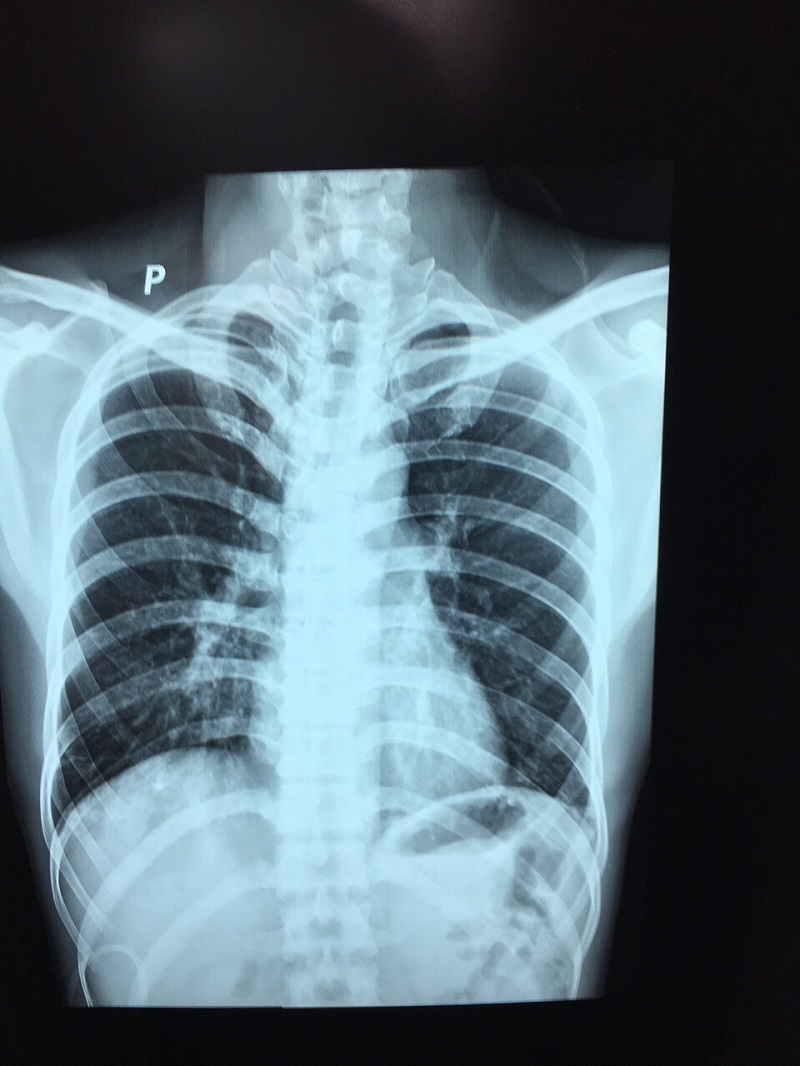

Theo người nhà đưa người bệnh đến kể, người bệnh đang sửa điện của máy sục bị điện giật ngã xuống hồ nuôi tôm, được người nhà vớt lên và đưa vào Trung tâm Y tế cấp cứu. Người bệnh vào khoa trong tình trạng vật vã kích thích, vã mồ hôi, chân tay lạnh, tím tái, khó thở nhiều, khạc ra bọt hồng, SpO2: 30 % huyết áp tụt Người bệnh được chẩn đoán: Phù phổi cấp – Bỏng điện

Đây là trường hợp rất nguy kịch. Các bác sĩ, điều dưỡng đã khẩn trương cấp cứu người bệnh kịp thời tiến hành thở máy CPAP, truyền dịch, dùng thuốc vận mạch … Với tinh thần khẩn trương, chuyên nghiệp sau xử trí người bệnh đã dần ổn định: tự thở được, đỡ khó thở, chân tay hồng hào dần lên, SpO2 dần trở lại bình thường

Hình ảnh người bệnh: